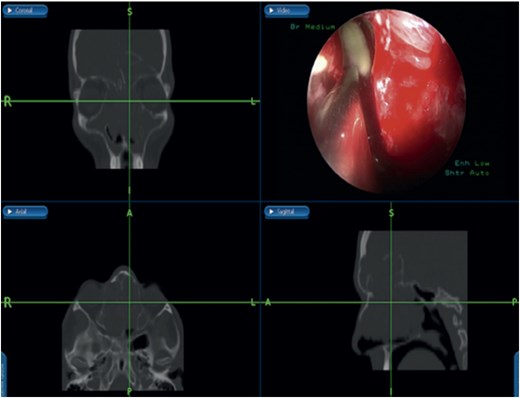

Bilateral extensive nasal polyposis was removed, and pus was drained from the ethmoid sinus cavities using a microdebrider (Fig. 2). Draf type IIb procedure was performed bilaterally to facilitate frontal sinus drainage and ventilation. The procedure was followed by antibiotic-soaked irrigation and evacuation of both mucopyocele cavities. After 6 months, the patient came to the clinic for follow-up, and his repeated CT scans showed normal sinus aeration and complete resolution.

Bilateral frontal sinus showing infected nasal polyps, identified intraoperatively, and drained by image-guided endoscopic sinus surgery.